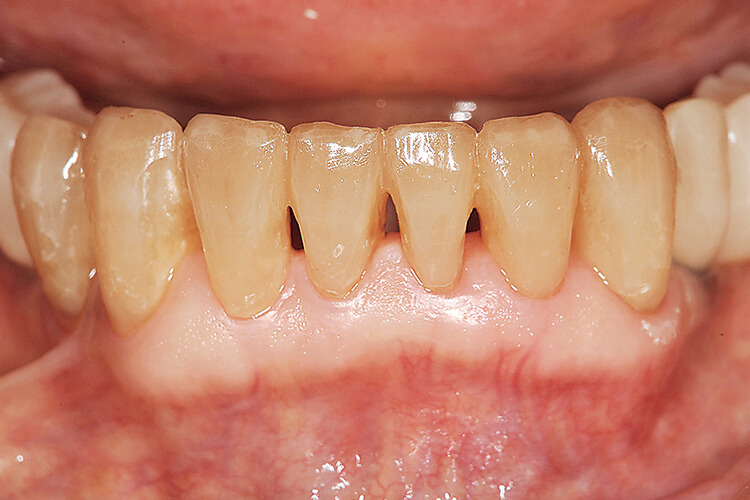

口腔内所見 鉤歯である 5 、 7 は動揺度が大きく咬合痛を有しており、咀嚼障害の原因となっている(図1)。

下顎残存歯には咬耗・楔状欠損が認められるが、支持組織は安定していることが観察され、比較的咬合力が強いが歯周病のリスクは低い患者であることが予測できる(図2)。

図1 初診時の正面観(半開口時)下顎中切歯間が顔面の正中に一致している。切縁に咬耗、歯頸部に楔状欠損が認められる。